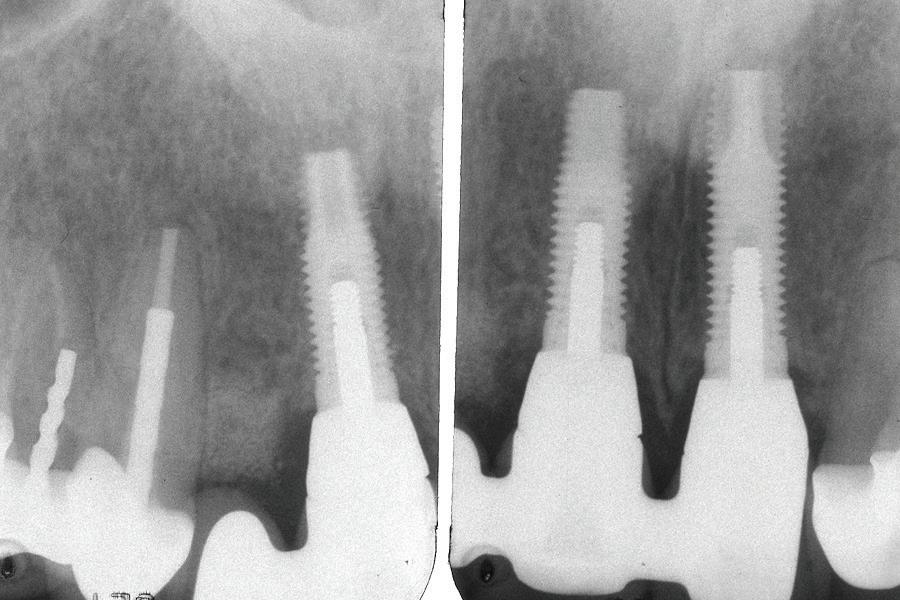

Un pacient caucazian în vârstă de 77 ani s-a prezentat la clinica autorului după cinci ani în care nu a fost la niciun control stomatologic. Examinarea clinică a arătat o pierdere semnificativă de os, parodontită cronică și multiple edentații care au destabilizat ocluzia. Pacientul a raportat sensibilitate la rece la nivelul primului molar drept inferior nr. 46, în special la ingerarea de lichide reci. Radiografia periapicală a confirmat constatările examenului clinic; în

plus, s-a detectat și prezența unei carii radiculare la nivelul rădăcinii distale a aceluiași molar, cu răspuns pozitiv la testul de sensibilitate (fig. 1-2).

Planul de tratament a început cu accent pe restabilirea sănătății parodontale. Într-o ședință ulterioară, odată cu îmbunătățirea stării parodonțiului, s-a efectuat restaurarea molarului nr. 46. Sub anestezie la Spina Spix pe partea dreaptă și

Figurile:

1. Situația clinică inițială.

2. Radiografia inițială.